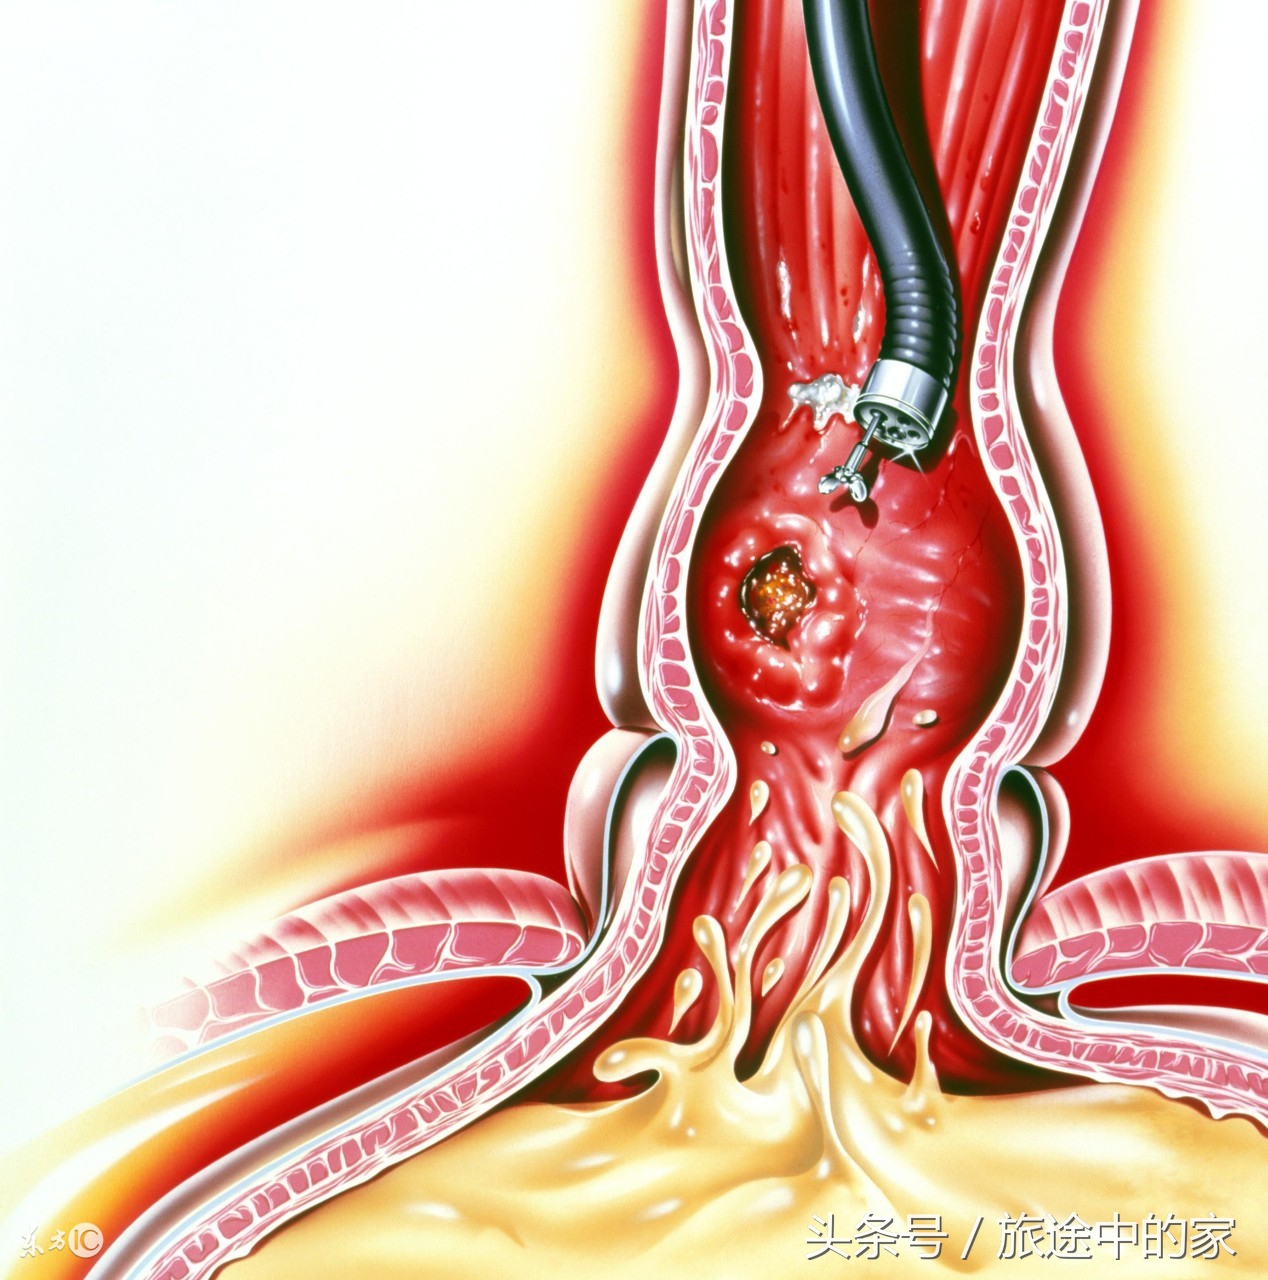

4)肠癌:早期症状是便血,也就是大便中混有血液或排出全血,另一个症状是大便习惯改变变,如大便时间、排便次数、大便性状、排泄时感觉等等;结肠癌病人的大便呈现鼻涕样、血性粘液便、腹泻与便秘交替出现,而非结肠癌病人的症状是腹泻、腹痛、大便多呈现带脓血的稀烂状;降结肠部位出现癌变时,症状是肠梗阻,如腹痛、腹胀和便秘。